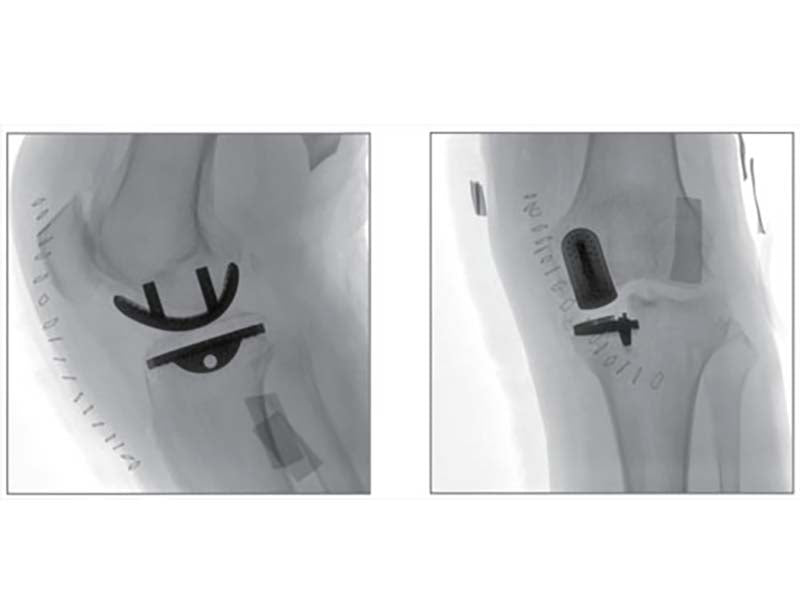

Compared to the conventional 9” image intensifier, a 9” x 9” flat panel detector is able to expand the FoV by 22%, providing more perspective for clinical diagnosis.

Eliminating distorted image caused by electron beam deflection, presenting actual vision of anatomical structure.

16 bits depth determines maximum 65536 greyscale value, providing HD resolution for revealing more anatomical details.